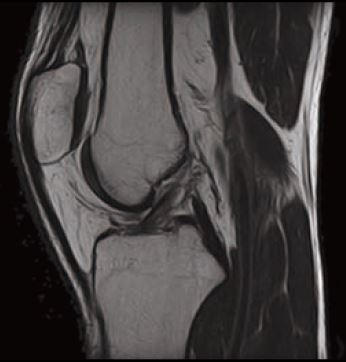

Випадок 1. Велике коліно

Жінка 67 років скаржиться на постійний медіальний біль у коліні.

• Відносно рясний внутрішньосуглобовий випіт.

• Остеоартритне ураження стегново-гомілкового суглоба в медіальній частині зі змінами субхондральної кістки, що може відповідати стресовому перелому.

• Дегенеративна сторона заднього рогу медіального меніска.

Рис. 1 Sg T2 FS, товщина зрізу 3 мм, роздільна здатність 0,4 мм.

Рис. 2 Sg FSE T1, товщина зрізу 3 мм, роздільна здатність 0,4 мм.